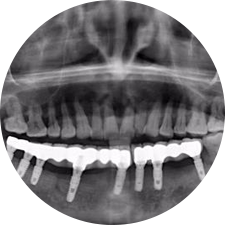

口腔種植是將人工牙根通過手術(shù)植入牙骨內(nèi),獲得牙槽骨牢固的支持,通過特殊的裝置和方式連接牙修復(fù)體,獲得與天然牙功能、結(jié)構(gòu)以及美觀相似的效果。

河北惟德口腔醫(yī)院擁有國內(nèi)豐富的半口/全口、即刻負(fù)重種植案例,十八年案例跟蹤分析,總結(jié)梳理出的各種不同類型的種植案例,Nobel種植體系針對(duì)半口/全口缺牙患者,通過4-8顆種植體可快速達(dá)到牙齒重建,不僅植入種植體較少,節(jié)省費(fèi)用,手術(shù)時(shí)間更短。

術(shù)前患者CBCT口掃1:1三維重建,模擬手術(shù)過程及預(yù)測術(shù)后治療效果,確定每顆植體植入的適合的種植位點(diǎn)、深度及角度,有效避免損傷頜骨重要解剖結(jié)構(gòu),提高手術(shù)準(zhǔn)確度與安全性。

Noble口腔種植體系基本不受年齡限制,適用于缺牙修復(fù),也適用于牙槽骨萎縮、骨質(zhì)疏松、高血壓、糖尿病、超高齡的患者,即種即用,只需少量微小種植體,便可輕松微痛快速重建全口咬合,特殊力學(xué)設(shè)計(jì),針對(duì)許多年紀(jì)較大,骨質(zhì)條件差,身體耐受力差的缺牙老人也能完成“即種即用”,受到廣泛好評(píng)。

惟德口腔種植體系是以患者感受為中心,取代傳統(tǒng)種植牙手術(shù)需要翻瓣、打孔、縫合,術(shù)前、術(shù)中、術(shù)后的繁復(fù)流程,采用3D導(dǎo)航微創(chuàng)準(zhǔn)確種植技術(shù),通過數(shù)字化CAD/CAM掃描技術(shù)獲得缺牙患者口腔數(shù)據(jù),以數(shù)據(jù)為基礎(chǔ)重建口腔模型進(jìn)行模擬種植。

術(shù)前將患者口內(nèi)的CBCT數(shù)據(jù)及咬合關(guān)系上傳到計(jì)算機(jī)中,建立1:1三維重建,模擬手術(shù)過程及預(yù)測術(shù)后治療效果,找出較佳種植位點(diǎn)、深度及角度,獲取實(shí)際種植體在頜骨內(nèi)的具體三維位置,有效避免損傷頜骨重要解剖結(jié)構(gòu),大大降低手術(shù)風(fēng)險(xiǎn),提升種植成功率。